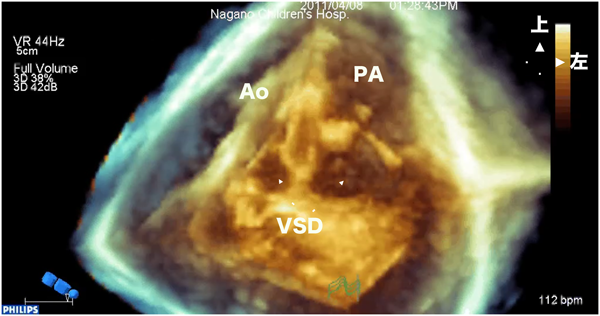

例えば図2では,肋骨下のwindowから心室中隔欠損を描出した両大血管右室起始症の画像である.バイプレーンモードや実際に探触子をその場所で傾けて目標部位:心室中隔欠損と周囲構造物:三尖弁,肺動脈弁,大動脈弁のすべてがよく描出できているのを確認する.さらに2D画像上でfocus,gain,dynamic rangeなどの調整を行う.このとき心室中隔欠損を正面からみた2D画像(en face view)を基本に3D画像をフルボリュームモードで取り込む.このように収集前に2D画像でよく確認することが非常に大切である.

図2 両大血管右室起始症の肋骨下断面像

VSDを中心においてなるべくすべての構造物が鮮明に描出されているwindowをみつけ,収集の基本windowとする.VSD: 心室中隔欠損,RV: 右室,LV: 左室,MV: 僧帽弁,PA: 肺動脈弁,Ao: 大動脈弁

両大血管右室起始症例で実際のクロッピングをしてみる.図4左はvolume dataの右室前面をカット:クロッピングした3D画像である.大動脈弁の下の広い範囲でconus:漏斗部中隔が見える.その向こうに心室中隔欠損が確認できる.図4右は断面をさらに奥に進めると肺動脈弁とその下の大きな心室中隔欠損が確認できた.図5右上のように,心室中隔欠損を中心に矢状断面でもカットすることで前から大動脈,肺動脈,心室中隔欠損の順に並び,この画像からJatene手術をすれば左室から大動脈に狭窄なくルートがとれることがわかる.

図4 両大血管右室起始症の3D画像

左図は右室前壁をカットした3D画像で,右図はさらに奥行き方向にカットを進めた画像.Conusの後方に肺動脈そして肺動脈弁下VSDがある.Ao: 大動脈,RA: 右房,RV: 右室,LV: 左室,VSD: 心室中隔欠損,IVS: 心室中隔